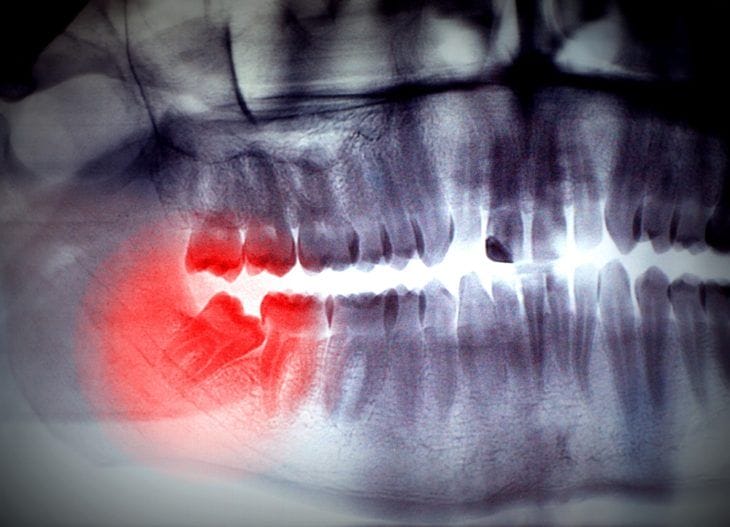

Sooner or later, most people will need to get their wisdom teeth removed. It might just be a matter of time before you need to get your own taken out – but how do you know when to say goodbye to those pesky teeth? Often it is a dentist who will decide when you need to get them extracted, by looking at x-rays to determine whether they will cause problems or are at risk of decay.

They normally grow through (erupt) during the late teens or early 20s and can often cause issues because there’s simply not enough room in the mouth for them to come in properly. Due to the lack of space the teeth can come through at an angle or only partially through the gum. This is what is known as impacted wisdom teeth and more often than not are the wisdom teeth that need to be removed.

Impacted wisdom teeth can cause pain, damage to other teeth and other dental problems, including overcrowding of the existing teeth and impaction, either into the neighbouring teeth or into the gum. However, not all wisdom teeth will cause immediate problems and even if they are impacted it might be painless.

One of the most noticeable signs that you need your wisdom teeth taken out is the pain and irritation both at the tooth site and when you open your mouth. Your wisdom teeth usually erupt between the ages of 17 and 21, making them the last to emerge in your mouth and therefore the most common teeth to become wedged-in or impacted. As there is not enough room in the jaw or mouth for them to emerge, instead of coming in straight they can come in sideways, tilted or misaligned in the jaw, pressing up against the teeth in front of it.